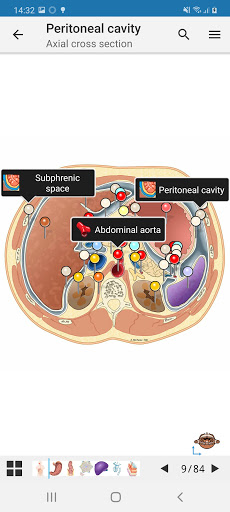

e-Anatomy memiliki lebih dari 26.000 gambar yang berisi serangkaian gambar dalam tampilan aksial, koronal, dan sagital serta radiografi, angiografi, gambar diseksi, bagan anatomi, dan ilustrasi. Semua gambar medis diberi label dengan cermat, lebih dari 967.000 label tersedia dalam 12 bahasa termasuk Terminologia Anatomica Latin.

- Gulir set gambar dengan menyeret jari Anda

- Perbesar dan perkecil

- Ketuk label untuk menampilkan struktur anatomi

-Sebuah pictogram sekarang hadir pada setiap gambar dan mewakili orientasi tubuh saat ini